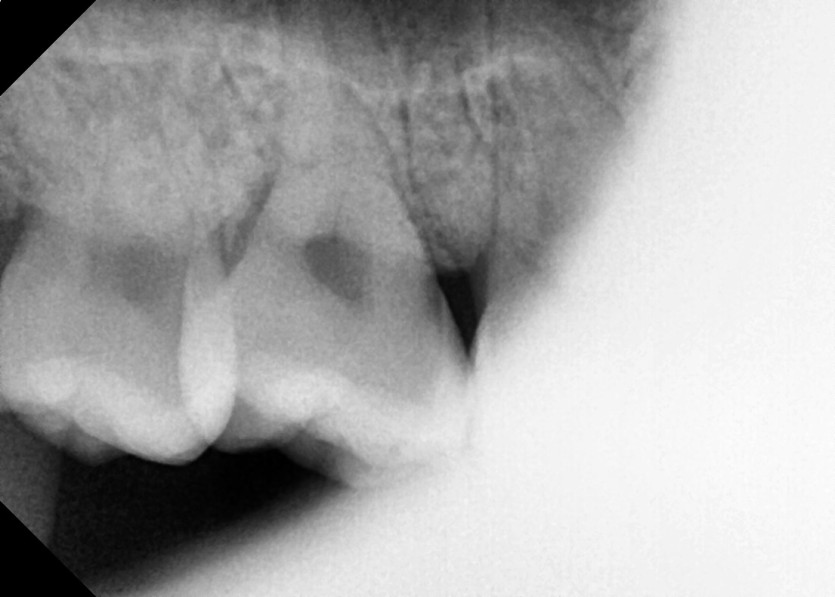

#18,48 사랑니 발치

구강 외과 전문의가 당일 발치했습니다.